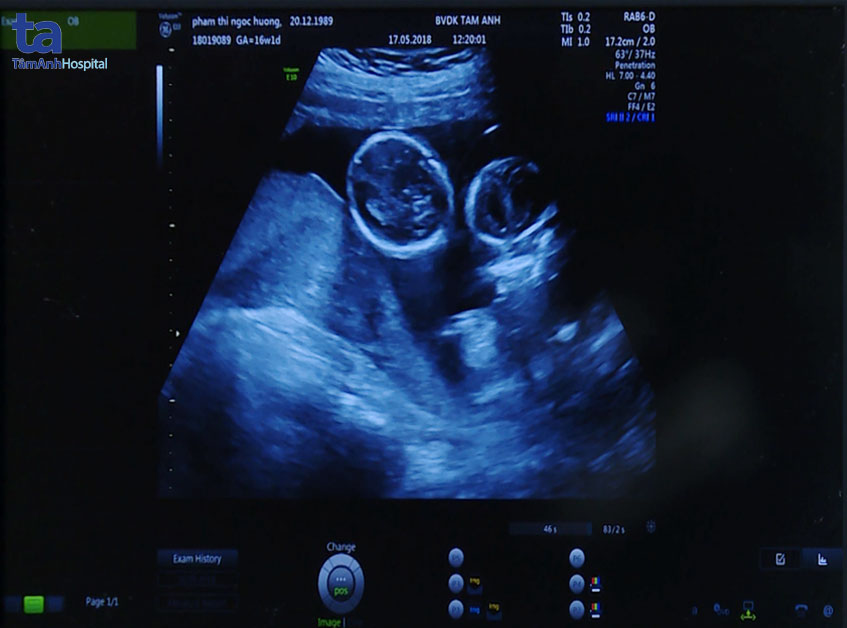

Bác sĩ Hiền Lê đang siêu âm cho thai phụ Phạm Thị Ngọc Hường (ảnh cắt từ clip)

Qua siêu âm, bác sĩ xác định thai 1 tương đương 15 tuần; thai 2 tương đương 15 tuần 4 ngày; thai 3 không có tim thai, chỉ có một phần thân và hai chi dưới. Thai bất thường do không có tim, không tự nuôi dưỡng được mình, phải “sống nhờ” bằng quả tim của thai bình thường. Quá trình bơm máu đó dẫn đến tình trạng thai bất thường lớn nhanh với tốc độ khủng khiếp, còn thai bơm máu dần dần suy kiệt khiến thai bên cạnh cũng suy kiệt theo. Tình trạng của bệnh nhân lúc này vô cùng nguy cấp. Nếu không phẫu thuật kịp thời, cả 3 em bé có thể không giữ được…

Hình ảnh tam thai trên màn hình siêu âm